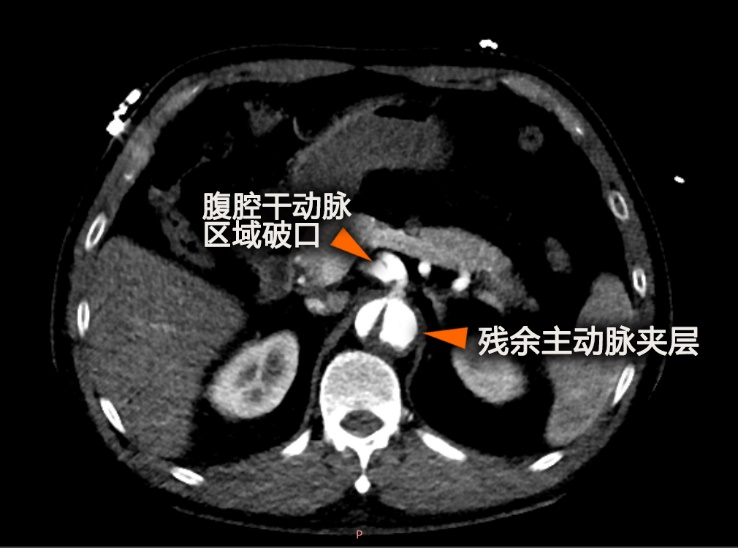

夹层术后残余破口:另外一位51岁男性患者,三个月前胸主动脉夹层术后复查发现支架远端仍有破口,假腔扩大威胁左肾供血,常规覆盖破口会导致器官缺血。

在3D模型引导下,于覆膜支架上精确预开四个窗口(对应内脏器官血供的:腹腔干动脉、肠系膜上动脉、左右肾动脉),并加固。

在杂交手术室,将预开窗支架精准输送到位,精细调整确保窗口与分支血管开口完美对齐,通过窗口植入分支支架重建血供,最后释放主体支架隔绝病变。术中运用“束径技术”(暂时约束覆膜支架为半释放状态,便于微调),避免并发症。